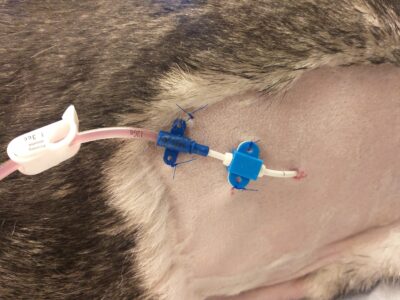

thoracostomy tube placement

thoracostomy tube placement -

pneumothorax - post procedure

pneumothorax - post procedure -

pneumothorax

pneumothorax -